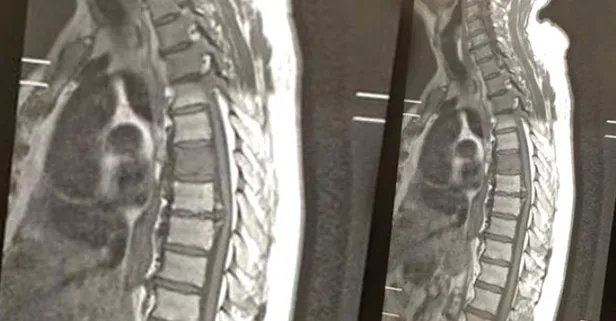

İngiltere'nin Liverpool kentinde akıllara durgunluk veren bir olay yaşandı. Daha önce yeme borusu kanseri tedavisi gören 70 yaşındaki Peter Cavanagh, 3 yılın ardından yendiği yemek borusu kanseriyle yeniden mücadele etmek zorunda kaldı. Omurgasını da etkileyen rahatsızlığı için röntgen çektiren adam, sonucu gördüğünde 50 yıllık eşi Tess ile birlikte gülmeye başladı.

Çünkü röntgen filminde 'cocker spaniel' cinsi bir köpeğin sureti gözüküyordu. Bu büyük bir tesadüften başka bir şey değildi. Görüntü hakkında şakalar yapan yaşlı adam, İngiltere gazetelerinde gündem oldu. Peter Cavanagh, "Ailemle köpeğin cinsinin beagle mı, spaniel mı olduğunu tartıştık ama bence kesinlikle spaniel. Burnu tam olarak, kanserin vücudumu etkilediği yerde" dedi.